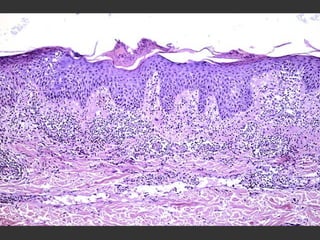

Histopathology

Early changes   Dilatation and congestion of vessels Mild perivascular lymphocytic infiltration

Psoriasis